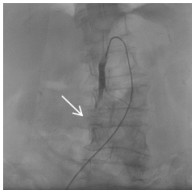

消毒右侧腹股沟区,经右侧股动脉入路。经穿刺点置入5F血管鞘,0.035 -in导丝引导5F Cobra导管进入SMA近端,造影(造影剂速度4~6 mL/s,时间3~4 s),明确病变位置及肠系膜远端血供情况。造影可见SMA近端呈夹层样改变(图 2细箭头示),空肠动脉分支近端呈假性动脉瘤样改变(图 2粗箭头示),虽然有夹层出现,但SMA主干全程尚通畅。更换8F血管鞘,应用导管导丝技术送入肝素涂层血管内覆膜支架(7 mm×25 mm)覆盖于夹层段并造影,发现病变段未完全封闭(图 3细箭头示)。主要由于为尽量减少支架对远端正常分支血管的影响,第一枚支架长度略短,因此再植入一枚支架(8 mm×25 mm)与第一枚叠加。再次经SMA造影,发现SMA主干内对比剂滞留(图 4),SMA中主干远端及其分支血管未显影。同时患者出现腹痛加重、气促、心率减慢至约40~50次/min,血压高压达到180/100 mmHg,考虑患者发生急性动脉血栓形成。紧急予面罩吸氧,静脉注射阿托品肌0.5 mg。经导管于SMA应用尿激酶25万U、肝素3 000 U进行持续灌注,灌注时间约5~8 min。应用球囊(8 mm×50 mm)扩张支架。最后再次经SMA造影,可见SMA主干近端再通,夹层瓣膜及其附近病变空回肠血管未再显影。病变远端空回肠动脉分支大部分恢复通畅(图 5粗箭头示),但SMA主干远端部分血管仍有部分未溶解血栓(图 5细箭头示),术后回病房每天皮下注射低分子肝素钙2 500单位,2次/d;患者腹痛症状当即减轻,生命体征恢复正常。

| 图 3 病变段植入第一枚支架后,夹层消失(粗箭头示),但空回肠动脉近端动脉瘤未完全覆盖,且SMA远端血管血栓形成(细箭头示) |